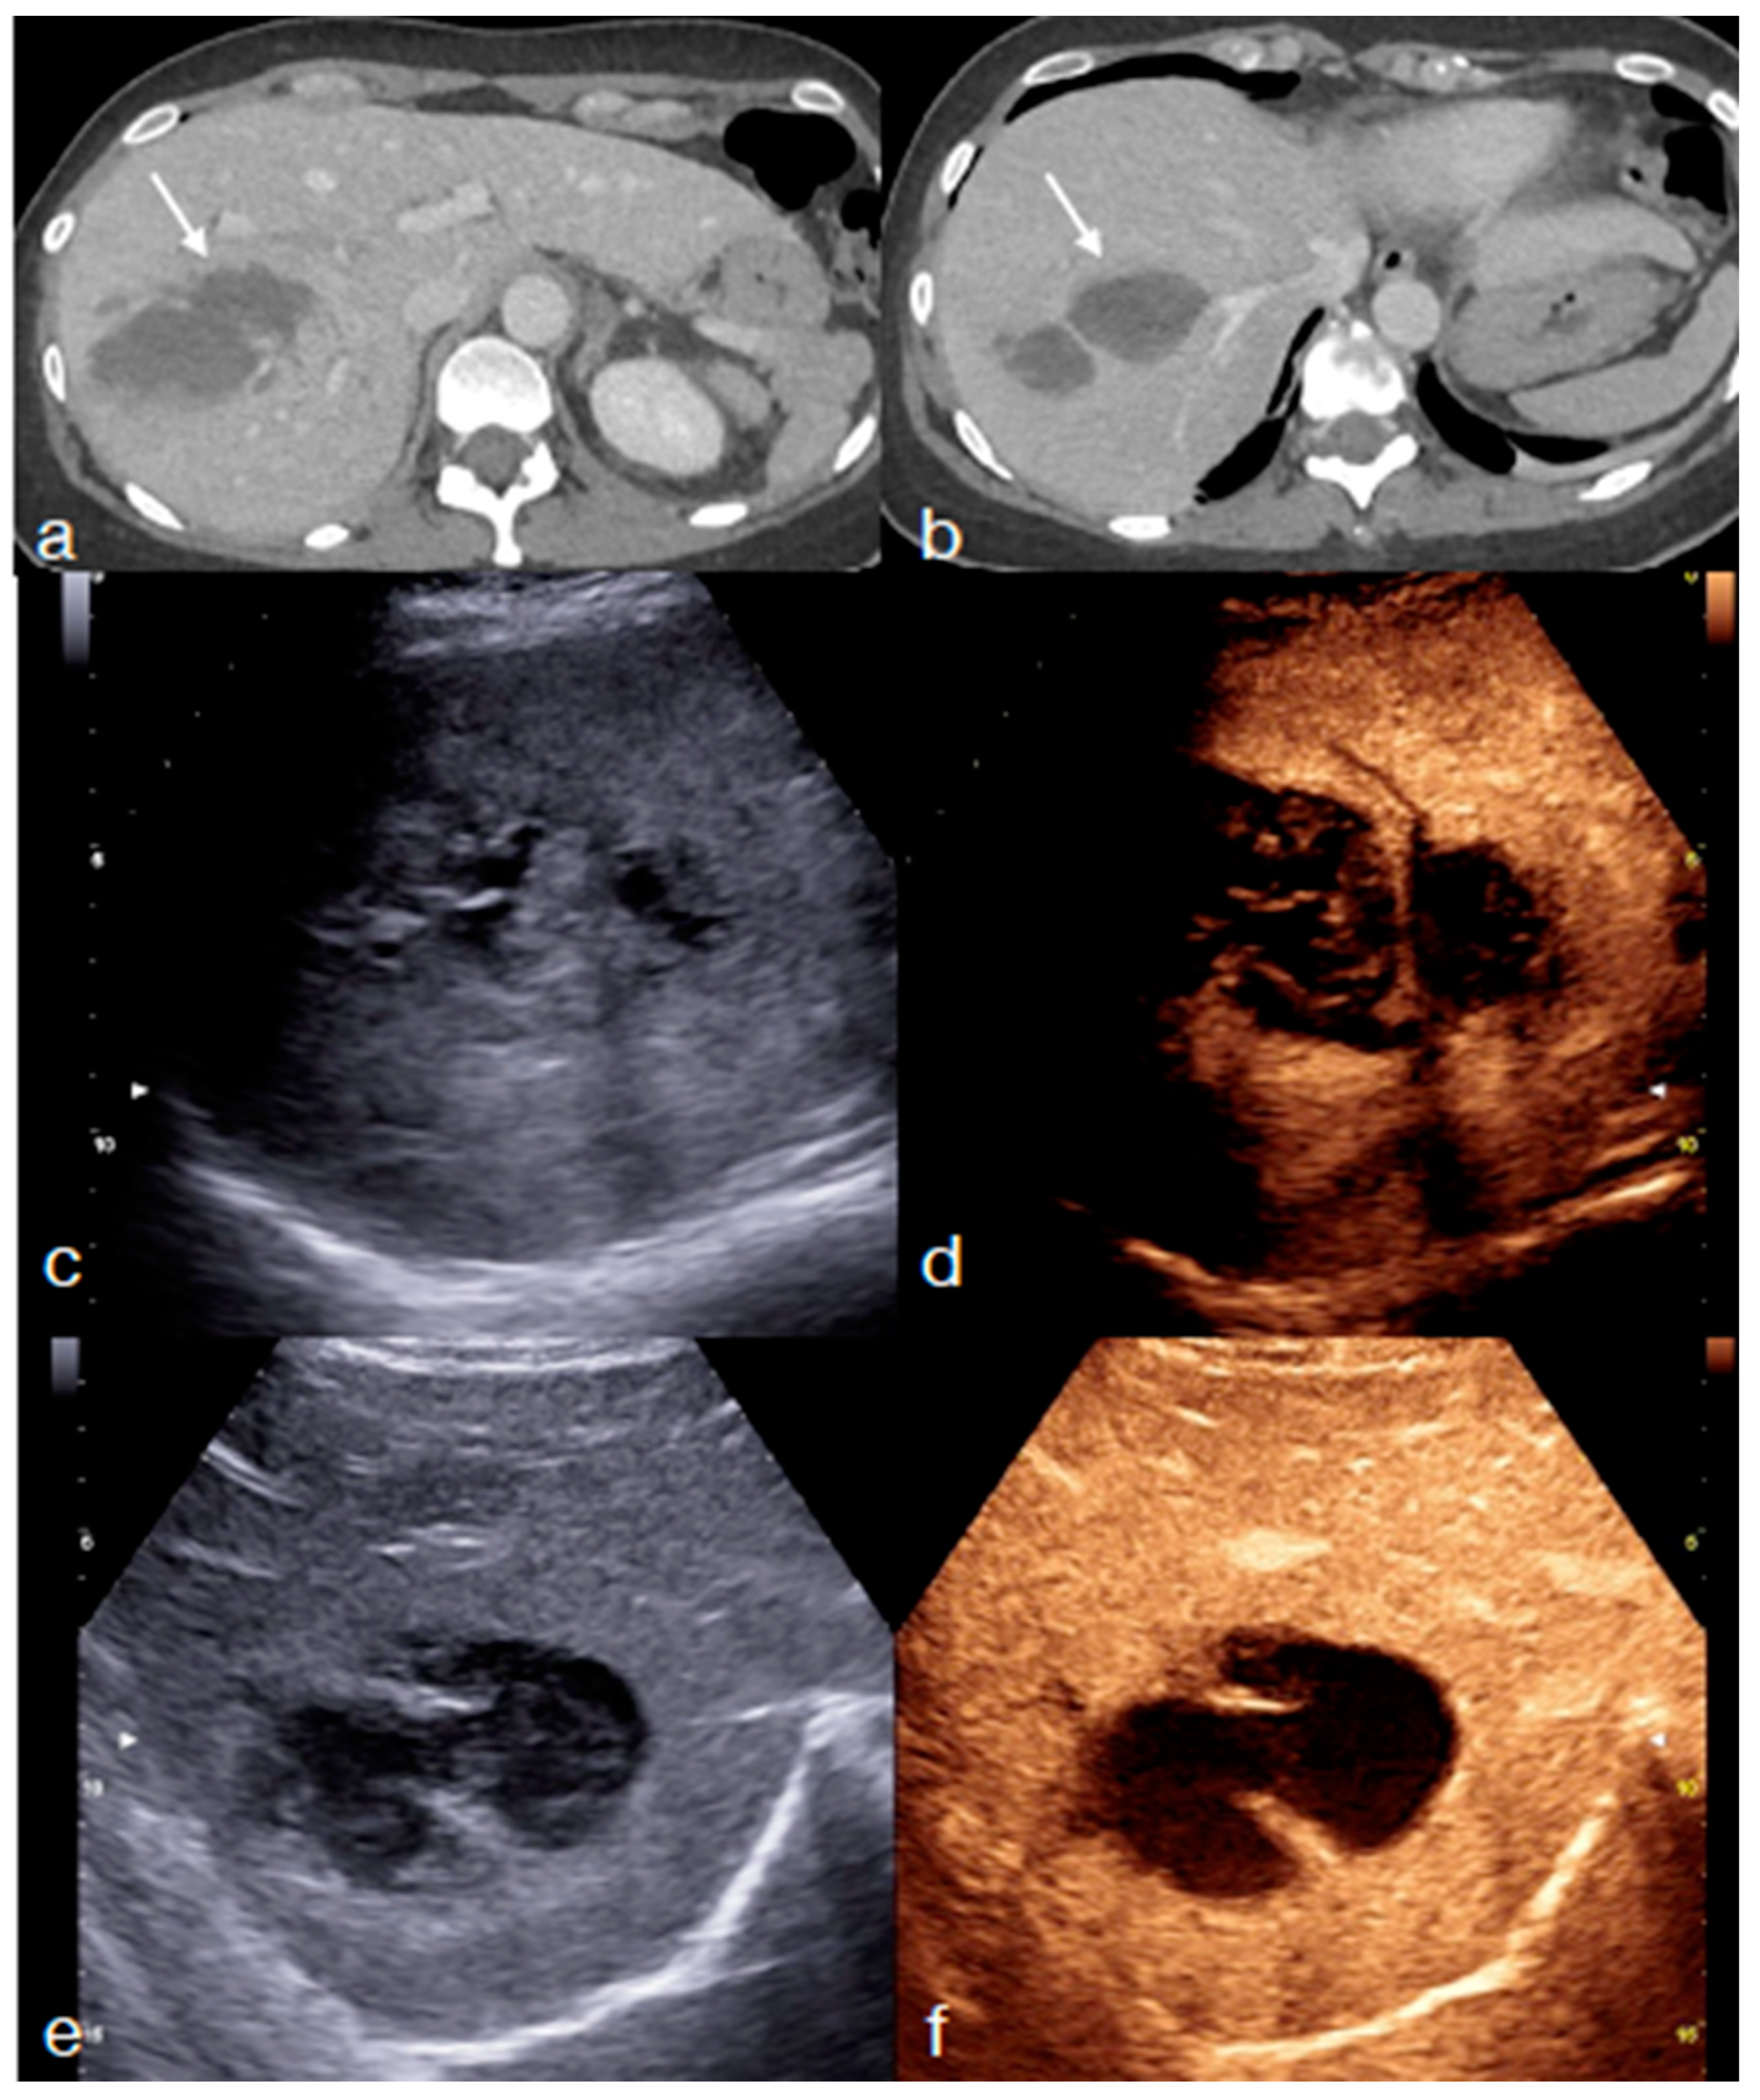

- Di Serafino, M.; Iacobellis, F.; Schillirò, M.L.; Ronza, R.; Verde, F.; Grimaldi, D.; Dell’Aversano Orabona, G.; Caruso, M.; Sabatino, V.; Rinaldo, C.; et al. The Technique and Advantages of Contrast-Enhanced Ultrasound in the Diagnosis and Follow-Up of Traumatic Abdomen Solid Organ Injuries. Diagnostics 2022, 12, 435. [Google Scholar] [CrossRef] [PubMed]

- Miele, V.; Piccolo, C.L.; Sessa, B.; Trinci, M.; Galluzzo, M. Comparison between MRI and CEUS in the follow-up of patients with blunt abdominal trauma managed conservatively. Radiol. Med. 2015, 121, 27–37. [Google Scholar] [CrossRef] [PubMed]